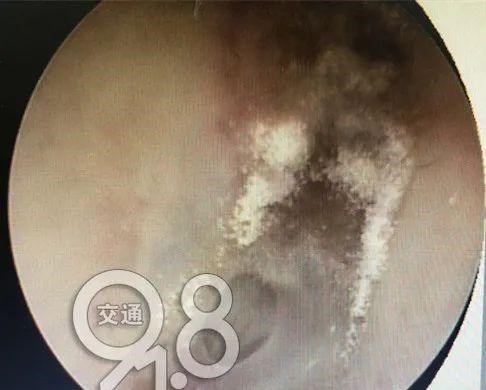

据医生介绍 , 原来 , 廖女士丈夫的外耳道真菌感染 , 白色絮状 , 形似木耳、蘑菇 。

杭州市某三甲医院耳鼻喉科主任陈志凌表示 , 采耳店的工具消毒不彻底、用不干净的棉签 , 若对外耳道的皮肤会造成损伤时 , 会容易引起细菌和真菌感染 。

▲医生提供治疗图